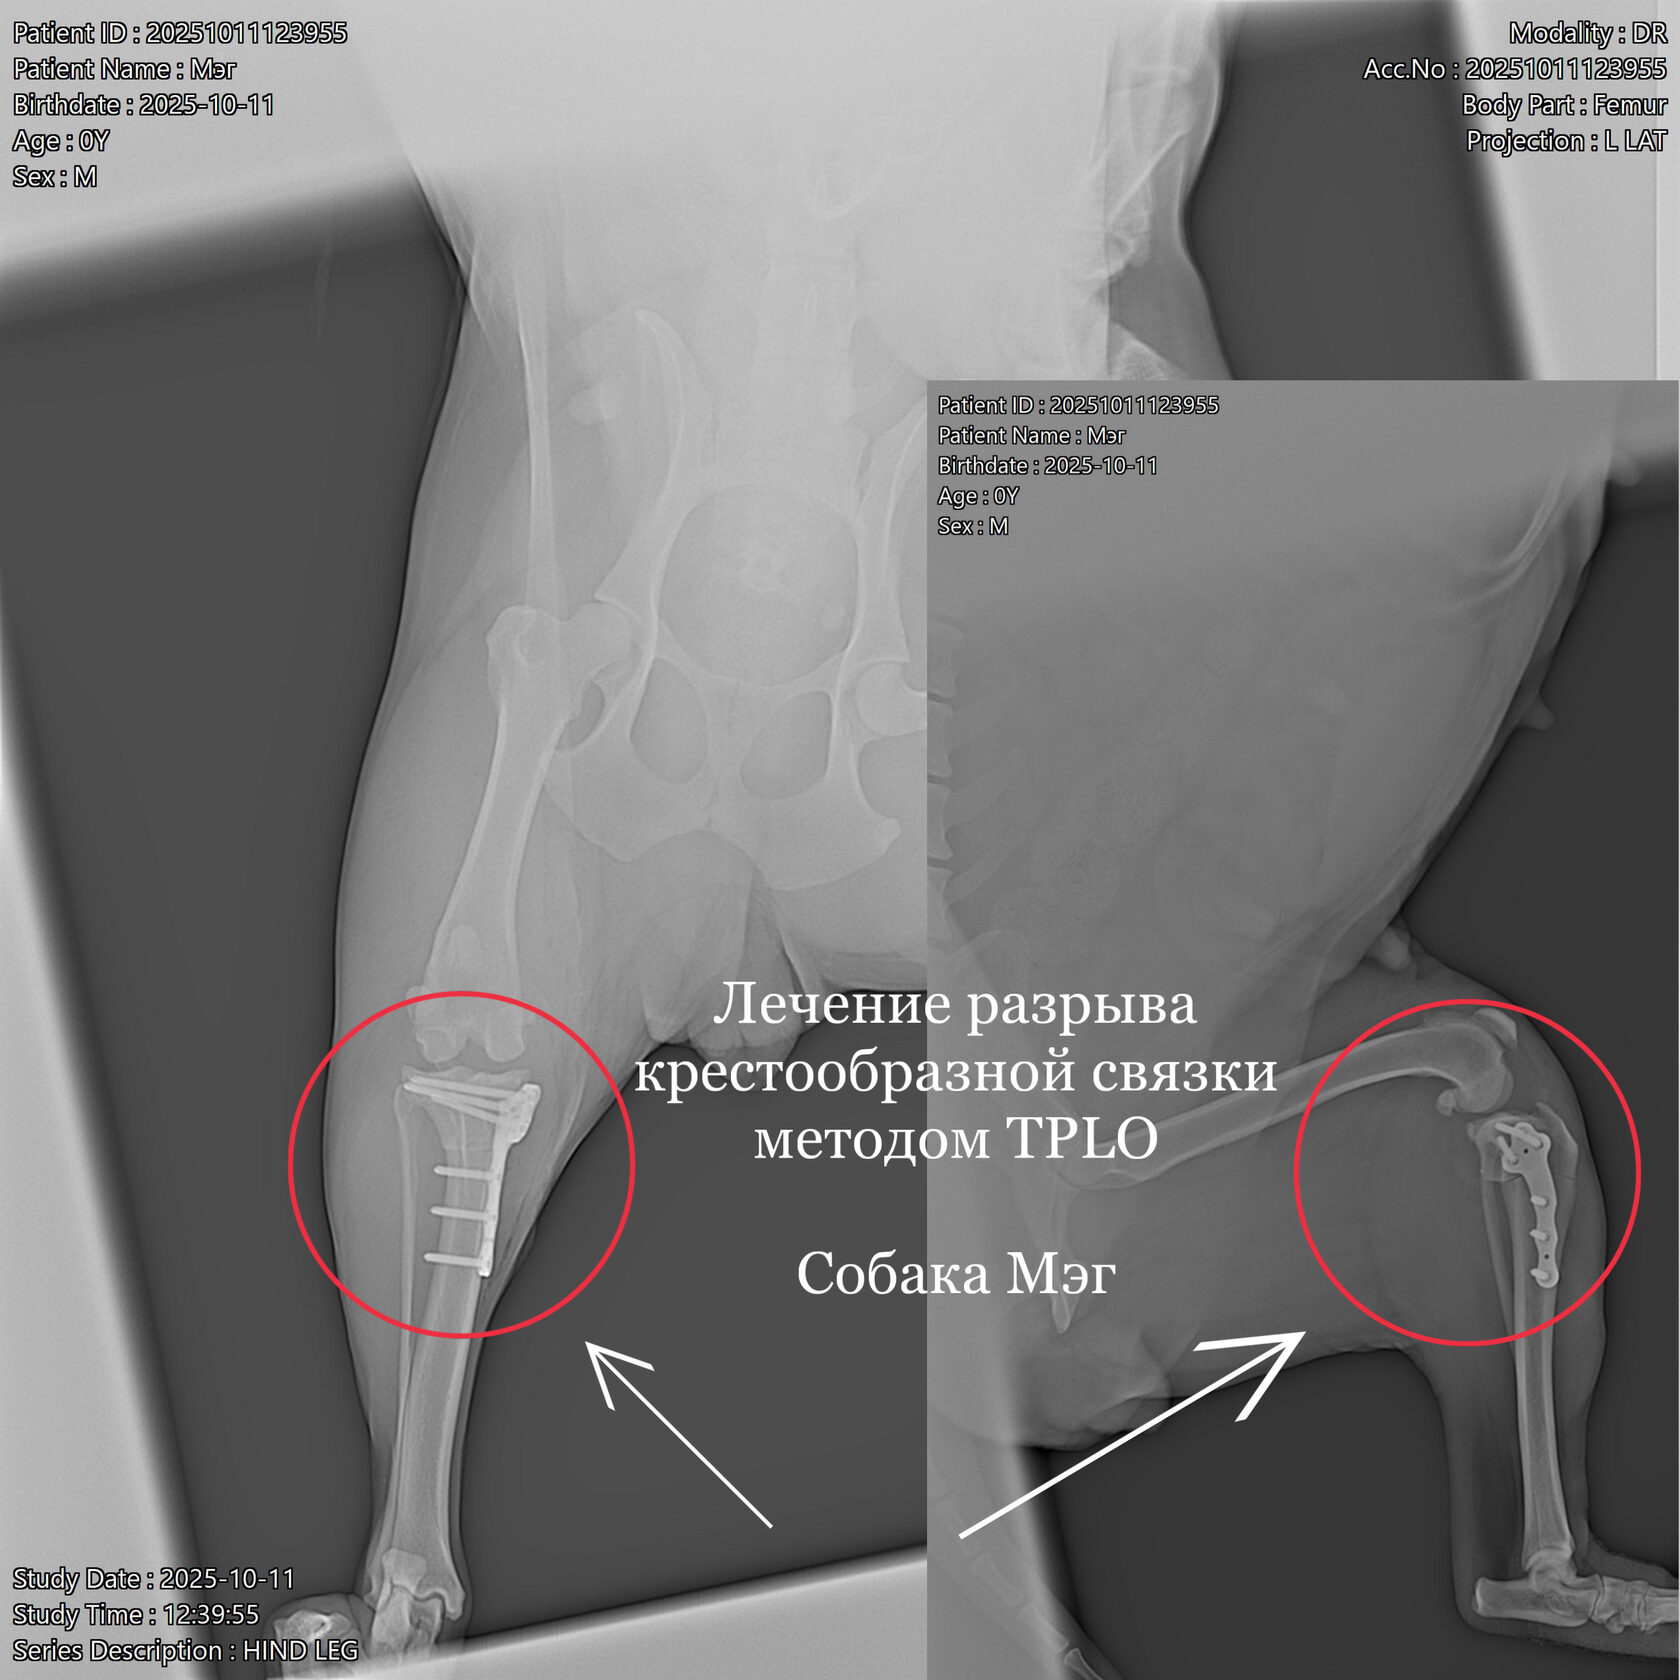

Ветеринарная травматология охватывает широкий спектр состояний: от вывихов и растяжений до сложных переломов. Ветеринар-травматолог применяет как консервативные методы (иммобилизация, медикаменты, физиотерапия), так и хирургическое вмешательство.

При сложных повреждениях используются остеосинтез, артроскопия и другие современные техники. Лечение проходит под контролем врача-анестезиолога, с учётом возраста и состояния животного.